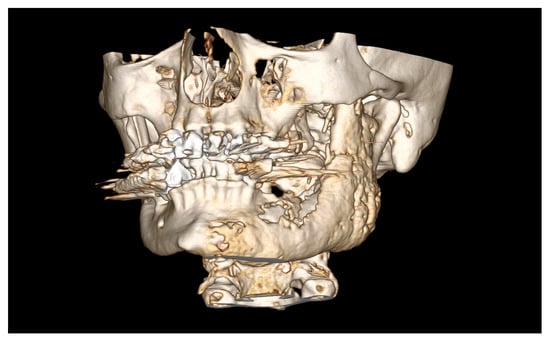

| Date | Intervention |

|---|---|

| 2000: | Initial diagnosis of prostate cancer with vertebral metastasis. Following radical prostatectomy with adjuvant radiotherapy and intravenous bisphosphonate therapy with zoledronate 4mg monthly and denosumab every 6 weeks. |

| July 2014: | Diagnosis of MRONJ in the right molar region of the mandible. Following mandibular box resection and protective plate osteosynthesis with a patient-specific plate. |

| August 2016: | Extraction of the second lower right premolar with smoothening of bony edges due to extraoral chronic fistula. |

| June 2017: | Removal of the reconstruction plate in the right mandible, re-osteosynthesis, and excision of a submandibular fistula on the right. |

| August 2018: | Partial mandibular resection with continuity defect and alloplastic reconstruction using a patient-specific plate, excision of a submental fistula |

| November 2018: | Cervical abscess on the right side with infected osteosynthesis material. Decortication and partial removal of the PSI. |

| December 2018: | Submental abscess on the left: extraoral abscess incision. |

| April 2019: | Cervical abscess in the right jaw angle with extraoral plate exposure and chronic-purulent fistula: extraoral abscess incision. |

| February 2022: | Paramandibular abscess on the left: intraoral abscess incision. |

| July 2022: | Submandibular abscess on the left: extraoral abscess incision. |

| September 2022: | Partial mandibular resection from the left mandibular angle to the right mandible, including the right temporomandibular joint, CAD/CAM-guided reconstruction with a bilateral free scapula flap with skin island, and patient-specific plate. In the course: